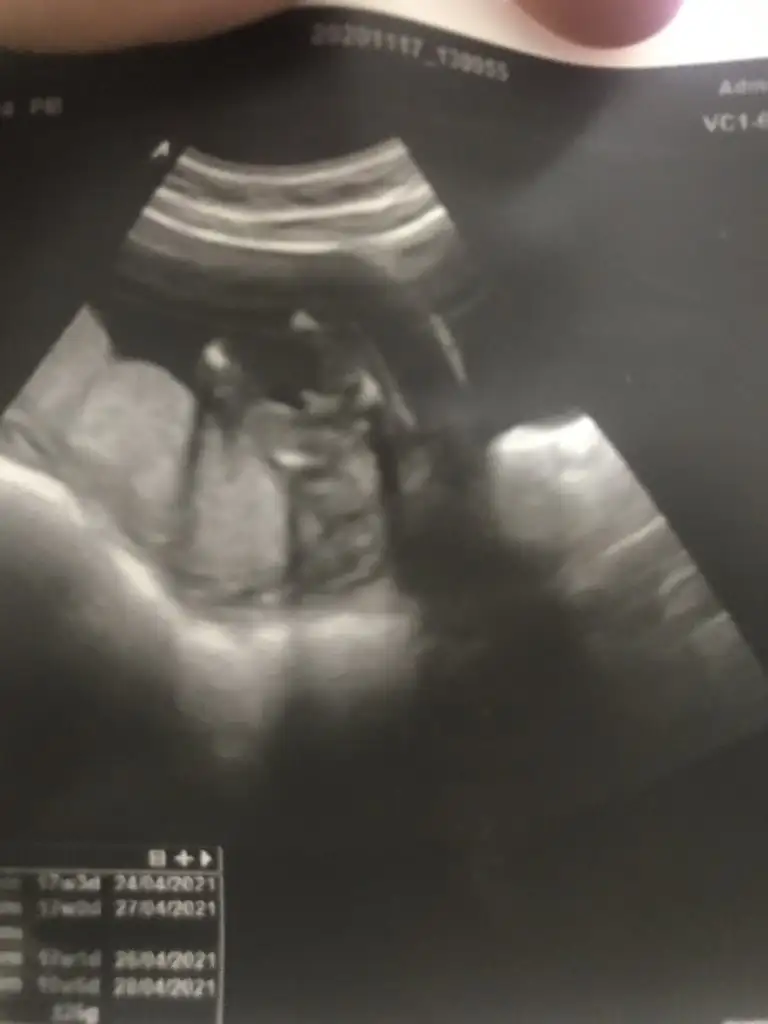

Evet erkek pipi orda duruyor yine benim dediğimMerhabaIkra meyra 11+4 görüntüye erkek gibi demiştiniz, doktorum kız gibi demişti ama kesin değildi. Bugün tekrar gittim 16+0 ultrason da 17 haftalık çıktı erkek diyor ama ben çok güvenemedim.Ultrason görüntüsü bacak arası mı çok anlamıyorum yorumlayabilir misin? Şimdiden teşekkürler

Kiz görünüyor başka USG varsa paylaşın 11 12 13 haftalar olmalıBenimkisinede bakar misiniz?Eki Görüntüle 2723115 Eki Görüntüle 2723116